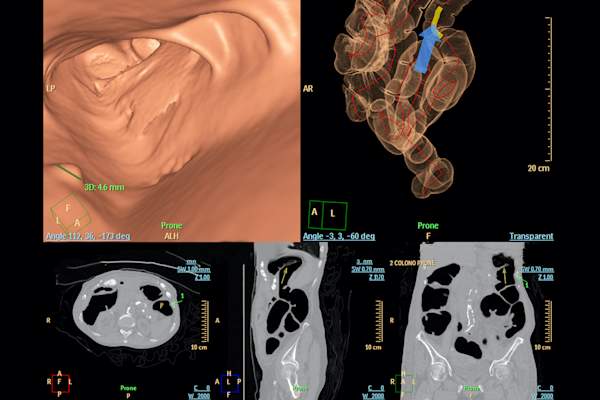

虽然没有一个尺寸适合的核心癌症治疗,但行动的过程通常取决于其阶段。“结肠直肠癌治疗是由癌症阶段引导的,”西雅图癌症联盟医疗肿瘤科医生和华盛顿大学肿瘤科副教授的医学肿瘤科医生。“该阶段由成像 - 例如CT扫描,结肠镜检查,MRI和病理学的组合来确定。(以及一如既往地,您的提供商将成为您的进入资源,以了解您最可行的治疗方案。)